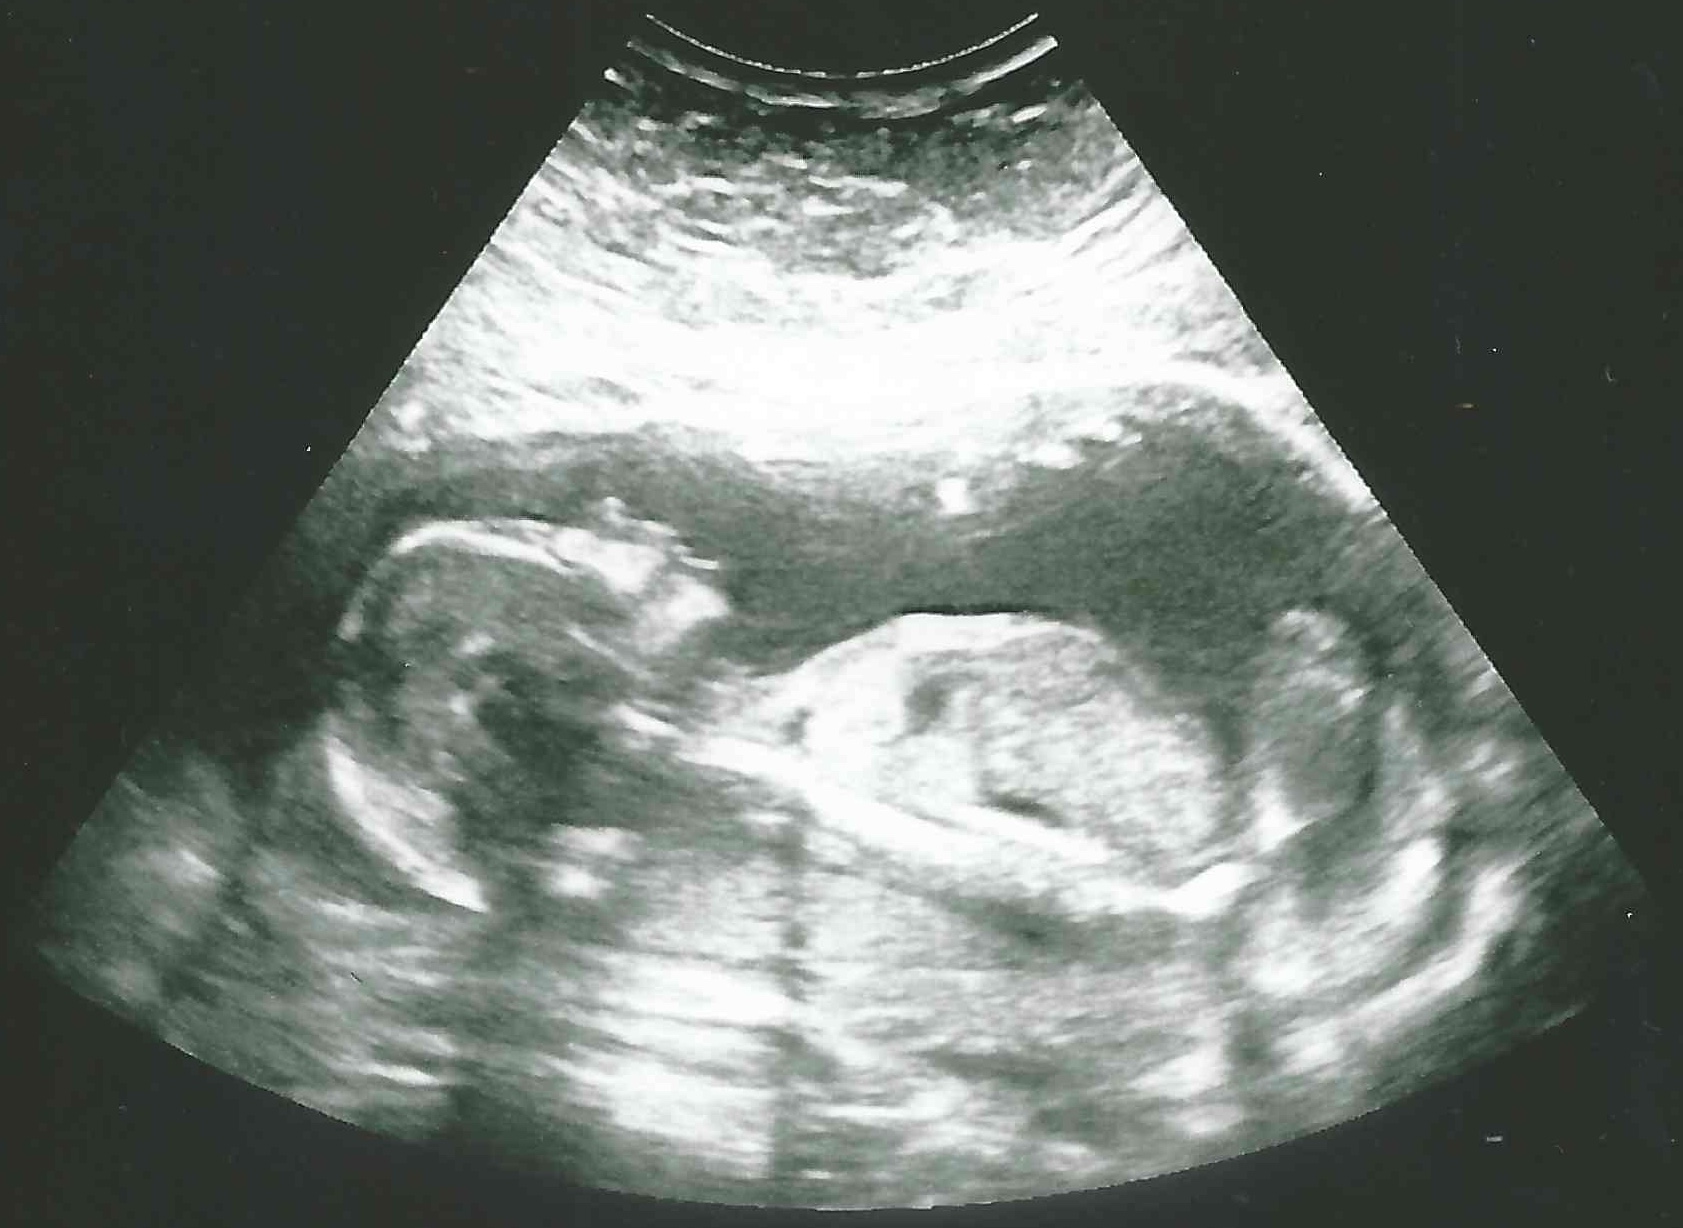

30 weken

Een echo na 30 weken.